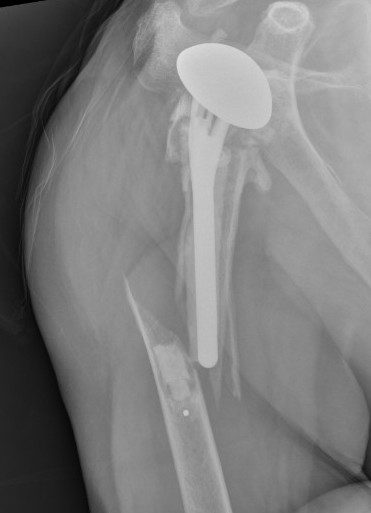

Superior migration of humeral head on xray

Shoulder Hemiarthroplasty Rotator Cuff FailureTSR Superior EscapeaTSA failed cuffTSR Failed Rotator CUff